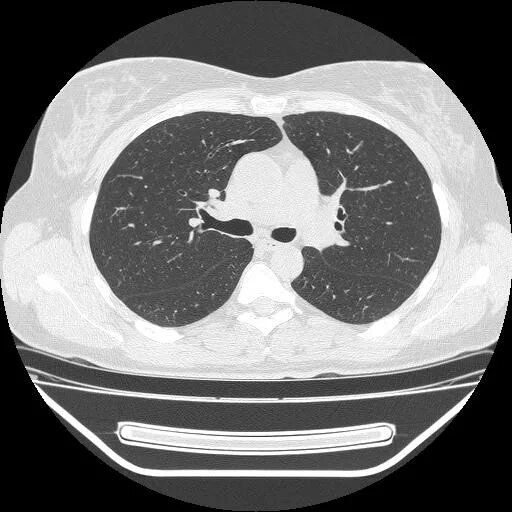

50 лет кт